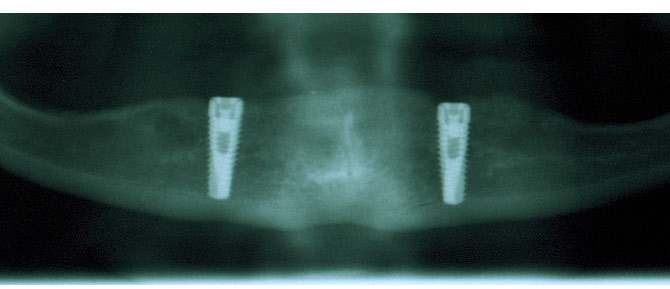

Voraussetzung für das Einbringen und eine lange Verweildauer eines Implantates ist ausreichend vorhandener Knochen. Abhilfe kann vielfach durch Knochenaufbauten geschaffen werden. Nebenstehendes Bild zeigt die zusätzliche Verknöcherung von Kieferhöhlenarealen, um ausreichenden Halt für die zwei Implantate zu schaffen.